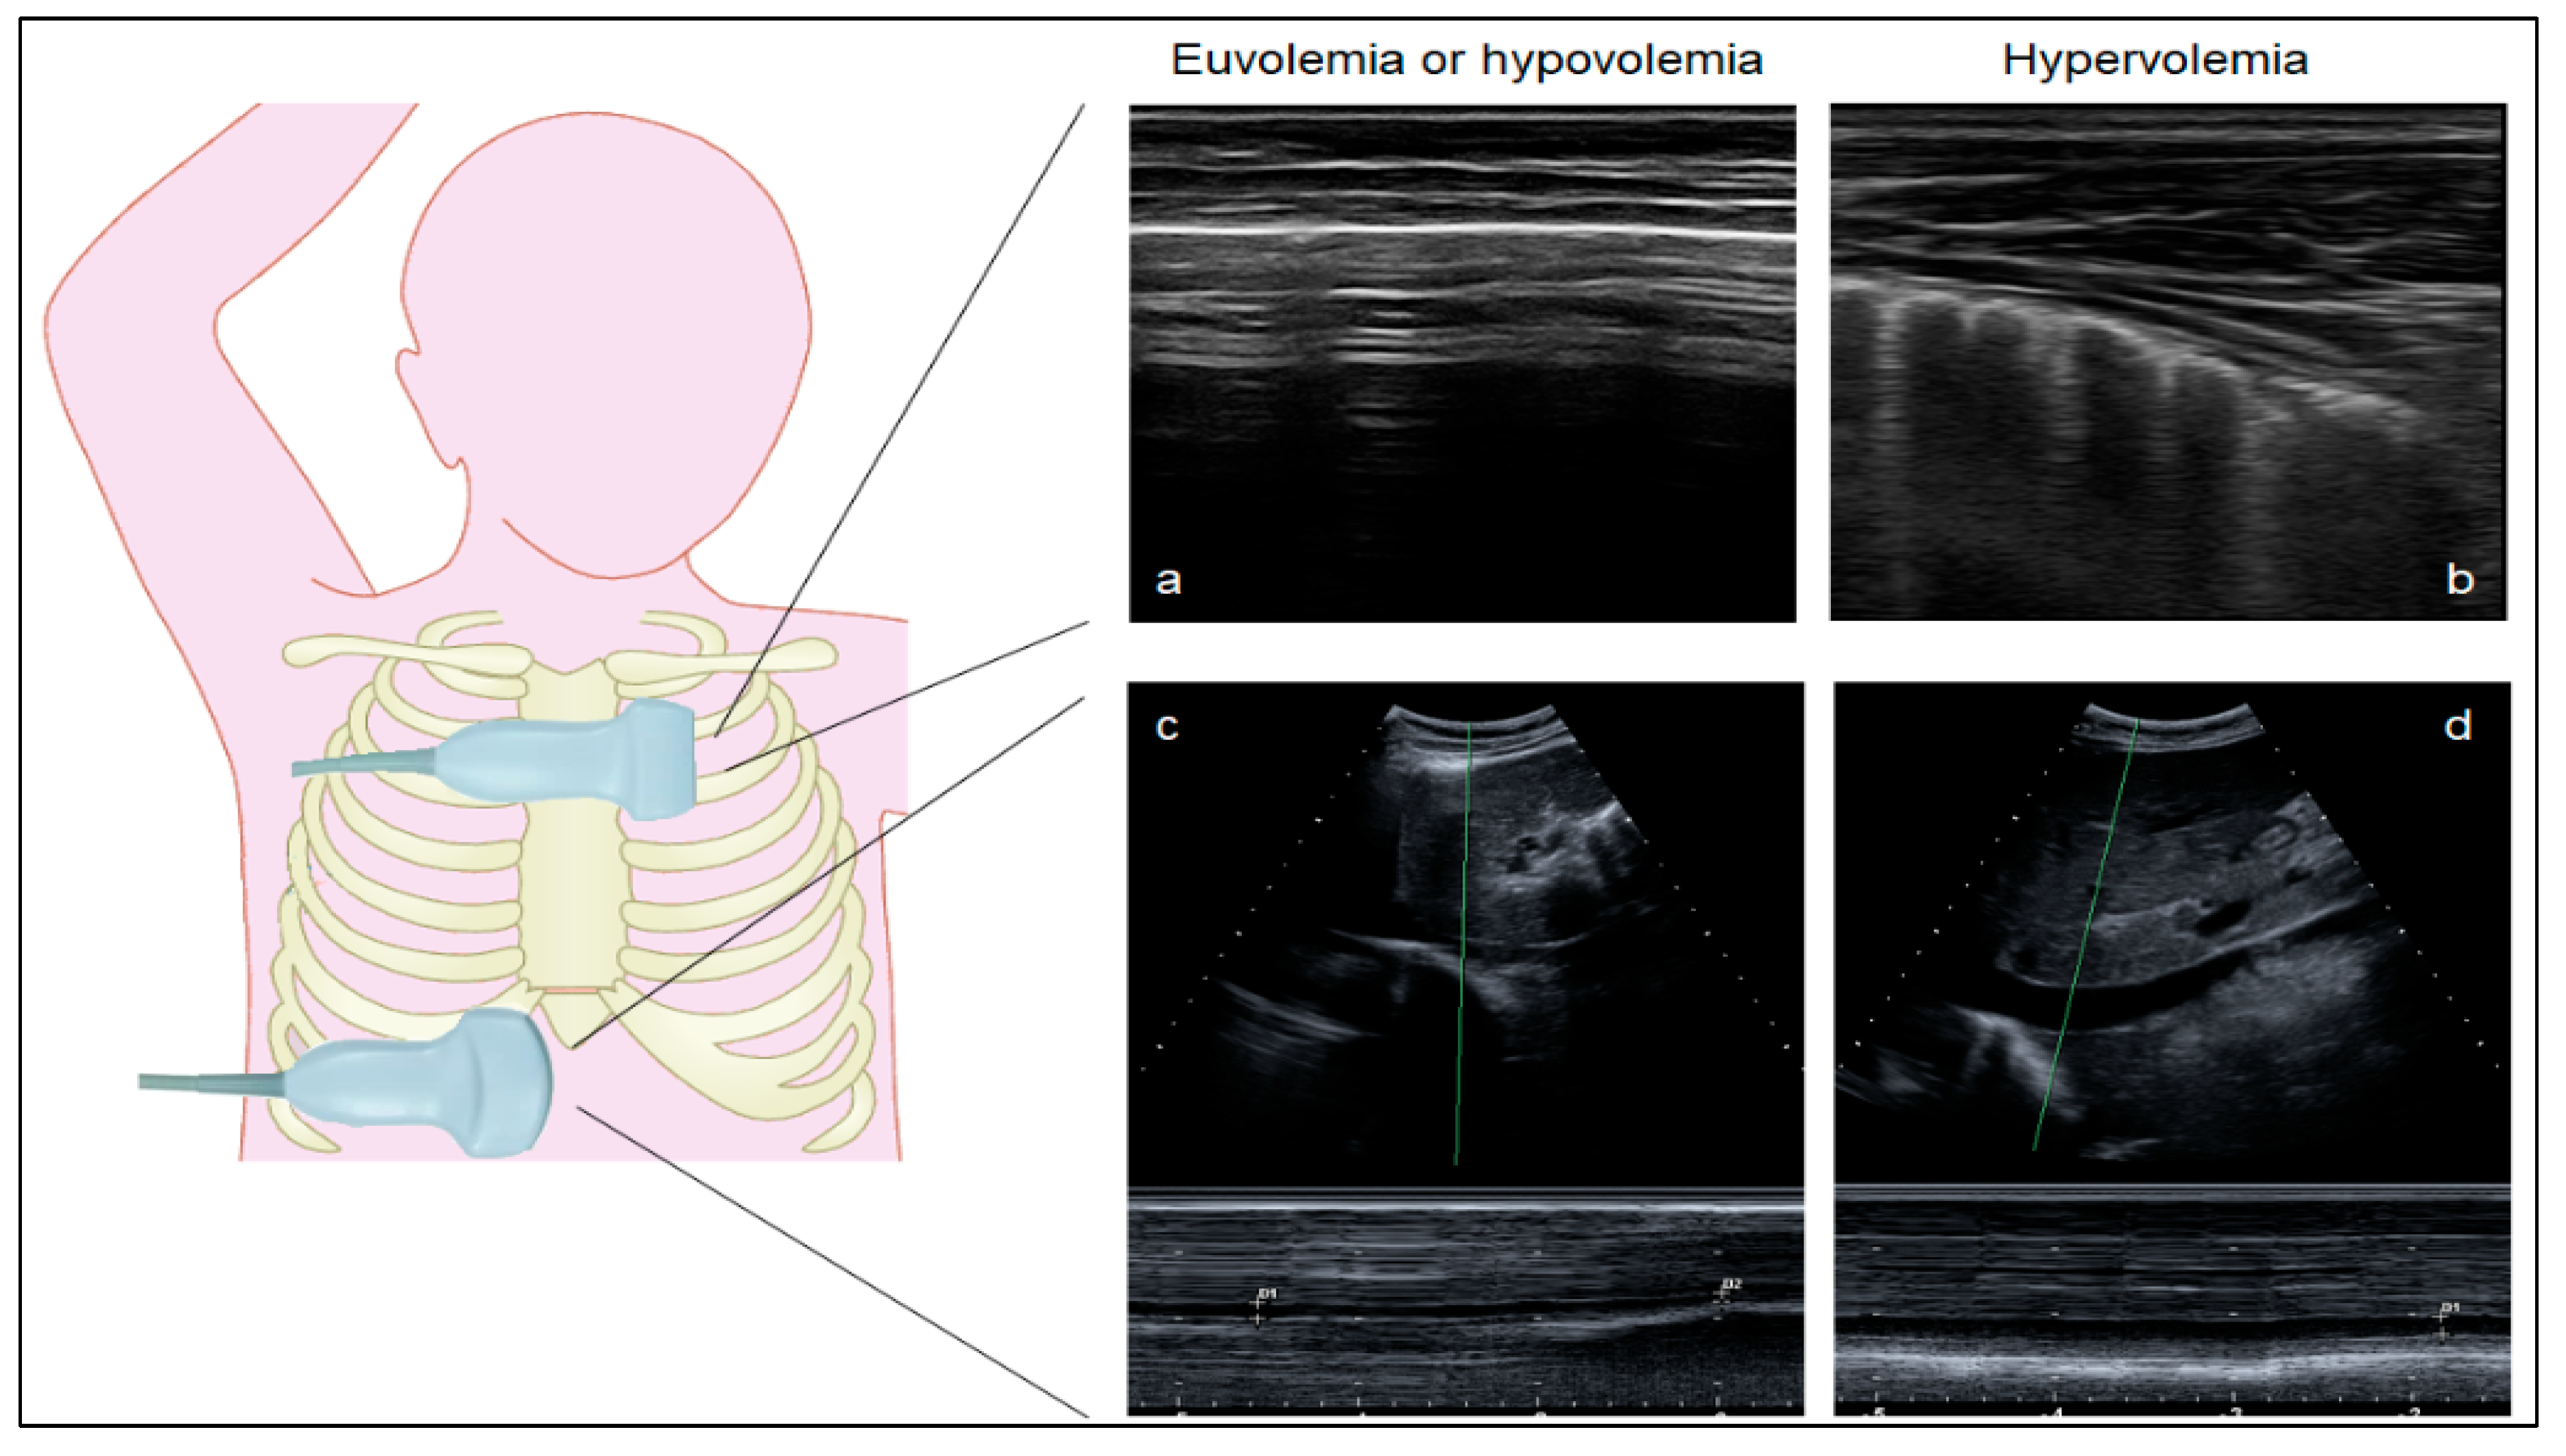

2.4. Ultrasound Measurements

3.1. Lung Ultrasound Can Distinguish Euvolemia and Lung Congestion in Children without STEC-HUS